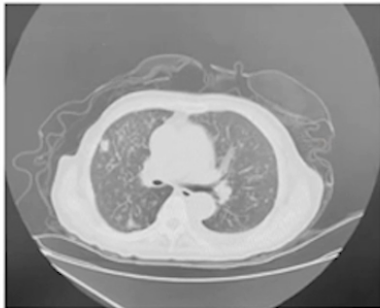

2024-5-10 CT平扫:全子宫+双侧卵巢切除术后,腹盆腔巨大囊性占位,腹盆腔内器官受压移位,腹壁软组织水肿。左肺上叶、右肺下叶占位,较前增大;双肺多发结节,较前明显增多、增大,均考虑转移进展。左侧胸腔积液并左肺下叶膨胀不全,较前新发。左侧第10后肋局部骨质破坏,较前新发,转移可能。